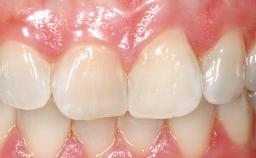

Late Flapless Placement of an Implant in a Maxillary Left Central Incisor Site

A 39-year-old male patient presented with a chief complaint of discomfort and gingival discoloration around his maxillary left central incisor. He was in good general health and was a non-smoker. His past dental history was significant because of the traumatic fracture of tooth 21 in a sporting accident at age 13. Initial dental treatment included endodontic therapy and a full-coverage restoration. The patient became symptomatic 5 years later, when structural failure of the tooth resulted in the dislodgment of the crown. Endodontic retreatment, apical surgery, and post-and-core restoration were performed.

Defining Characteristics One missing tooth to be replaced by an implant-borne crown

Esthetic Risk High